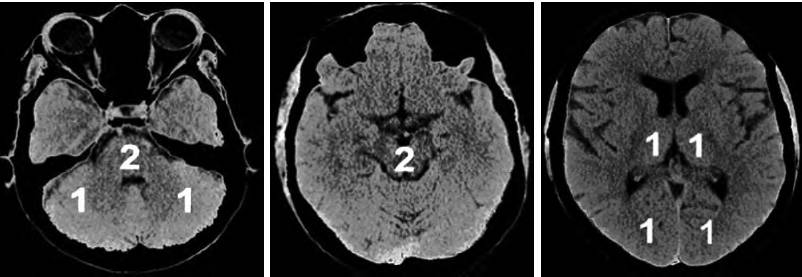

为评估后循环梗死患者早期梗死情况,PUE T Z等建立了评估后循环的AIS预后早期CT评分(pc-ASPECTS)。pc-ASPECTS总分也是10分:双侧丘脑和小脑各1分,双侧大脑后动脉供血区各1分,中脑和脑桥为2分(图2)。

图2 pc-ASPECTS评分中后循环供血区功能分区注:pc-ASPECTS:后循环急性卒中预后早期计算机断层扫描评分